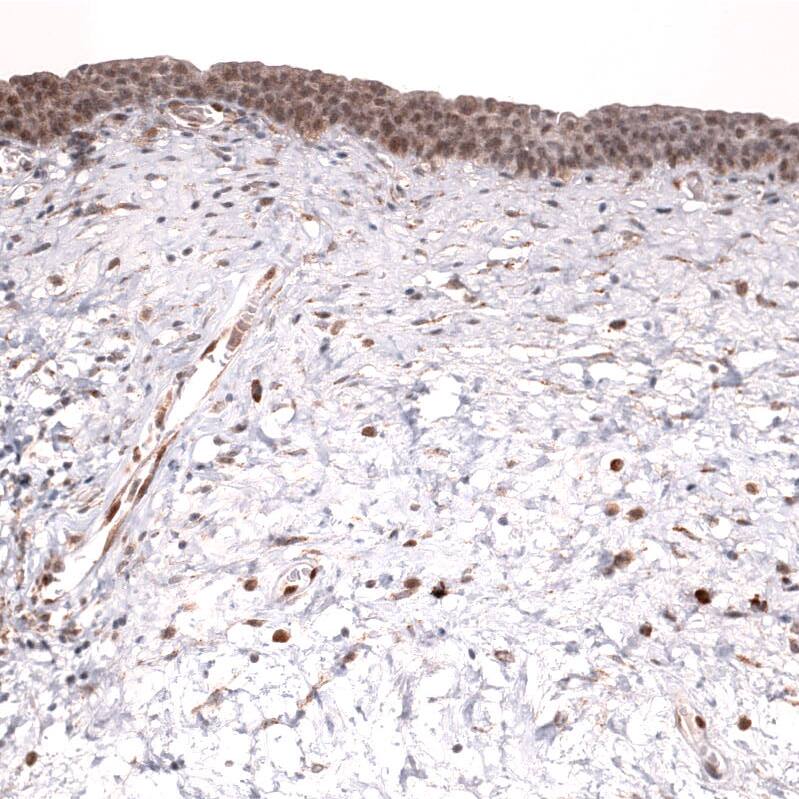

Immunohistochemistry-Paraffin: IL-33 Antibody (CL13438) [NBP3-24558]

Staining of human skeletal muscle shows no positivity in myocytes as expected.